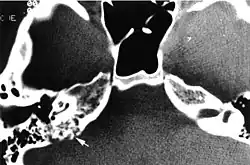

CT in patient with VHL syndrome through the petrous ridge demonstrates bone erosion at the site of the endolymphatic sac tumor, typical of the locally aggressive behavior of this tumor (curved arrow).

Imaging studies help to identify the tumor and the specific anatomic site of involvement. Magnetic resonance images show a hyperintensity (hypervascularity) of a heterogeneous mass by T1 weighted images. Computed tomography shows a multilocular, lytic destructive temporal bone mass, centered on the vestibular aqueduct (between internal auditory canal and sigmoid sinus).[1][6][7]